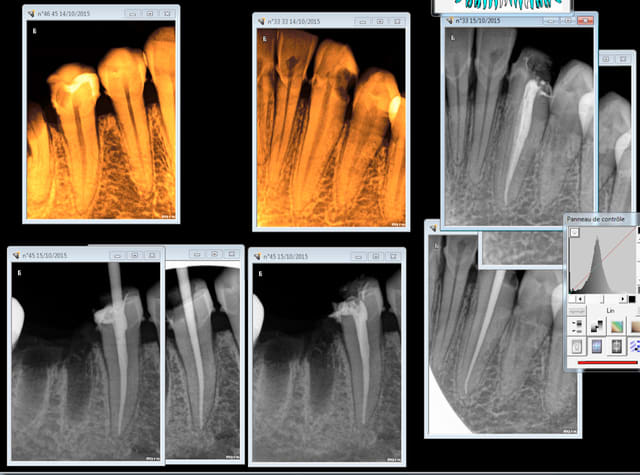

1h pour cette 41 (endo taille empreinte provisoire)

Quicksleeper 5 ostéocentrale en distal. Silence opératoire instantané et le léger engourdissement de la lèvre était dissipé à la fin de la séance.

SX sur entran, largo 3 sur double bague verte pour ouvrir l'entrée.

S1 sur endomaster alterné avec réciproc R 25 ( canal pas perméable du tout au cathétérisme à la lime 10) pour atteindre la LT.

Finition au R25.

Cone scellé au tubuli seal, thermo compaction mac spaden.

Empreinte en mordu.

Note : la 32 date de 2003 à cette époque j'alesais au 50 ca me prenait un peu plus de temps ! -)))))

Heuh, si je peux me permettre, tigabi, on a ici une belle lyse osseuse horizontale (age ou parodontopatie) contre-indiquant un peu l'intraseptale!!!.

L'intracorticale assez basse ou tout betement la para-apicale sont dans ce cas particulier des indications de choix pour nos anesthésies.

Premier echec en distal de cette 33. Ca rentre mais difficilement du début à la fin, on sent pas la pénétration "par étages" je pense vu l'épaisseur du septum qu'une trans corticale aurait été plus judicieuse.

Par contre en mésial de 44 septum large pas de soucis.

1 sur 15 mais indication de la technique mal posée. C'est quand meme curieux l'aiguille était à la garde pourtant mais aucune sensation de tomber dans un trou ni de descente par étages à la perforation.

en fait tu es resté dans la corticale